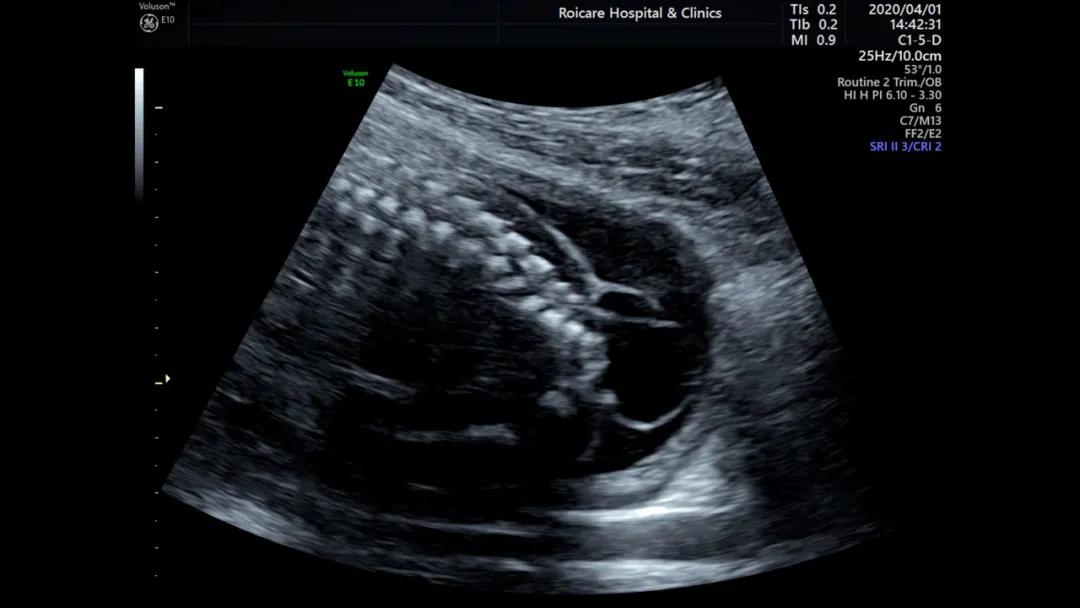

骶尾部脊柱裂伴脊髓脊膜膨出

开放性脊柱裂受累段脊髓神经损伤,可导致双下肢运动异常和大小便*禁失**;伴发脑室扩张或积水将影响运动、脑神经、认知功能。闭合性脊柱裂包括多种类型,即有包块型:脊膜膨出、脂肪脊髓脊膜膨出、脂肪脊髓裂、末端脊髓囊状膨出;无包块型:脊髓纵裂、终丝紧张、皮毛窦、尾端退化综合征等。